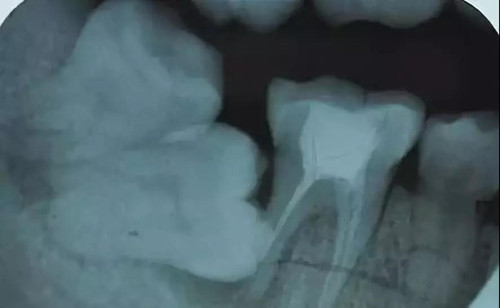

由于下颌第三磨牙与下颌管的关系密切,下牙槽神经损伤多由拔除下颌阻生第三磨牙导致,少数第三磨牙牙根与下牙槽神经血管束紧密贴邻,牙拔除后导致牙槽窝与下颌神经管相通,术后的出血通过交通进入神经管压迫下牙槽神经造成神经损伤或感觉障碍,若能在牙槽窝内神经管暴露处覆盖一层生物膜或填塞胶原塞即可有效降低术后神经受压损伤的可能性。

胶原塞因其良好的生物相容性并具有极强的黏附能力,可附着于牙槽窝与神经管相通处,隔绝出血对神经的压迫,从而达到预防神经损伤的目的。